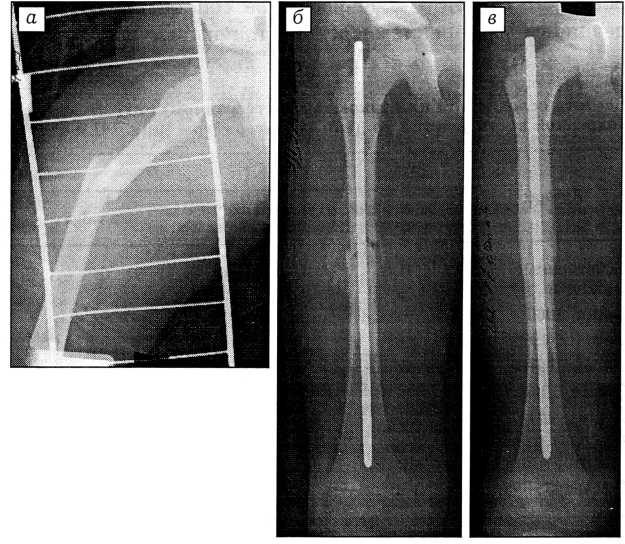

Интраоперационных осложнений в наших наблюдениях не было. Вторичных смещений костных фрагментов, их несращения или замедленной консолидации у детей после закрытого интрамедуллярного остеосинтеза не отмечено. Характерным было формирование веретенообразной мозоли, при этом она имела меньший объем у больных, оперированных в ранние сроки — на 3-5-е сутки после травмы (рис. 7).

Рис. 7. Рентгенограммы бедренной кости ребенка 6 лет (прямая проекция). а — до операции, б — после операции, в — через 6 мес.

Удаление имплантата осуществляли преимущественно через 6 мес после остеосинтеза.